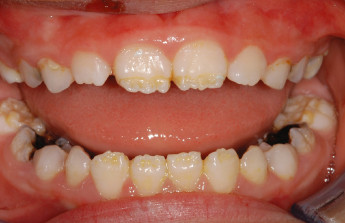

What Is Enamel Hypoplasia?

Enamel is the hard, protective outer layer of your teeth. Enamel hypoplasia is a defect of the enamel that only occurs while teeth are still developing. Still, it can affect both baby teeth and permanent teeth. The condition results in thin enamel, which makes your teeth vulnerable to dental decay.

The visual signs of enamel hypoplasia include white spots, pits, and grooves on the outer surface of the teeth.

Tooth enamel is the hardest substance in your body, but it doesn’t contain living cells and can’t repair itself or improve on its own. So, if you or your child has enamel hypoplasia, you’ll need to have a dentist monitor your teeth and act quickly to repair problem areas.

What are the symptoms?

Some of the signs of enamel hypoplasia are obvious, but others are more difficult to detect and may not be noticeable until they cause major dental problems. Having thin tooth enamel can lead to:

pits, tiny groves, depressions, and fissures

white spots

yellowish-brown stains (where the underlying layer of dentin is exposed)

sensitivity to heat and cold

lack of tooth contact, irregular wearing of teeth

susceptibility to acids in food and drink

retention of harmful bacteria

increased vulnerability to tooth decay and cavities.

What causes it?

Defective enamel development can be the result of an inherited condition called amelogenesis imperfecta, or congenital enamel hypoplasia, which is estimated to affect about 1 in 14,000 people in the United States. This condition can also cause unusually small teeth and a variety of dental problems. Congenital enamel hypoplasia can happen alone or as part of a syndrome affecting other parts of the body.